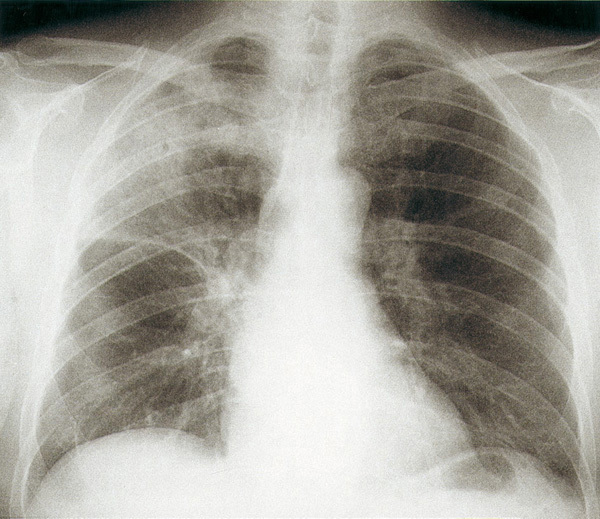

©La Revue du Praticien Radiographie de thorax de face. Pneumonie franche lobaire aiguë supérieure droite à pneumocoque.